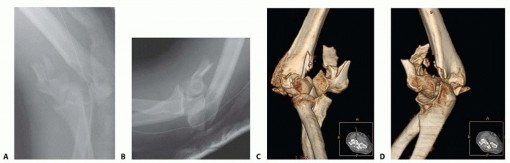

15 MIN READ Open Reduction and Internal Fixation of Pediatric T-Condylar Fractures يناير 2023 Read More